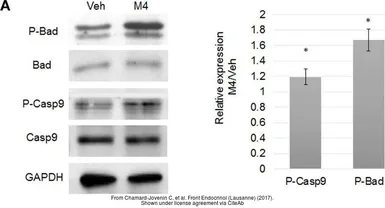

The data was published in the journal Front Endocrinol (Lausanne) in 2017. PMID: 29109696

The data was published in the journal Front Endocrinol (Lausanne) in 2017. PMID: 29109696